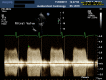

Figure 1

Continuous wave Doppler interrogation across the mitral valve prosthesis with loss of biphasic filling pattern (prethrombolysis).